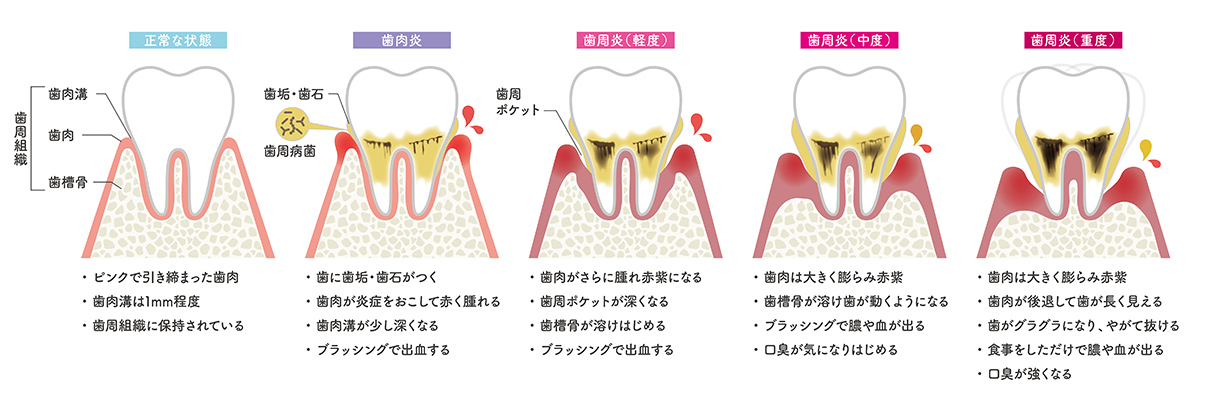

歯周病は歯茎の中に歯周病原菌と呼ばれる細菌が侵入し、徐々に増殖してその毒素が歯茎やその周りの骨を破壊してしまう病気です。

初期段階では自覚症状はほとんどなく、「歯周病かも」とご自身で気付いた時には、かなり進行した状態になっていることも少なくありません。

歯周病は日本人(成人)の約80%がかかっているといわれ、歯を失う原因の1位でもあります。症状は「軽度」「中度」「重度」の3段階に分類され溝の深さ(歯周ポケット)を測定することで歯周病の進行度合いを判断します。

早い段階から症状に応じた適切な治療を行うことで、歯周病の進行を防ぐことができます。